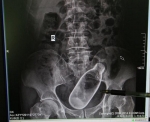

Врачам лучше говорить правду! Они как правило в своей практике много видали. Как-то был у друга в больнице, он хирург, так у них в ординаторской они повесили стенд с предметами, которые вытаскивали из пациентов. Кунц-камера отдыхает. Тем более рентген будут делать, все равно увидят...

Рентген - сила